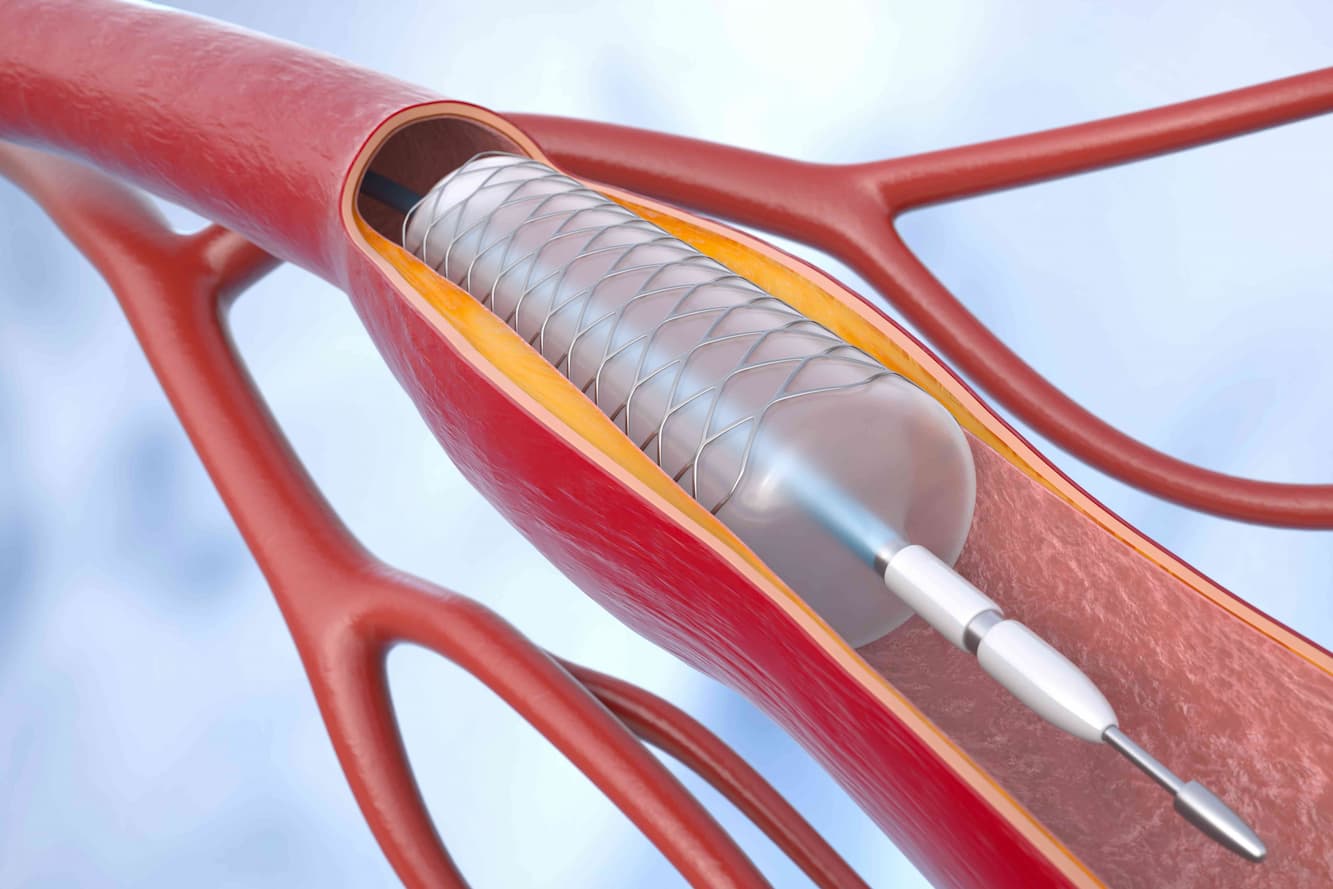

Cardiology plays a pivotal role in maintaining heart health, covering everything from regular check-ups to complex procedures. We partner with esteemed cardiologists from top hospitals.

Cardiology plays a pivotal role in maintaining heart health, covering everything from regular check-ups to complex procedures. We partner with esteemed cardiologists from top hospitals.